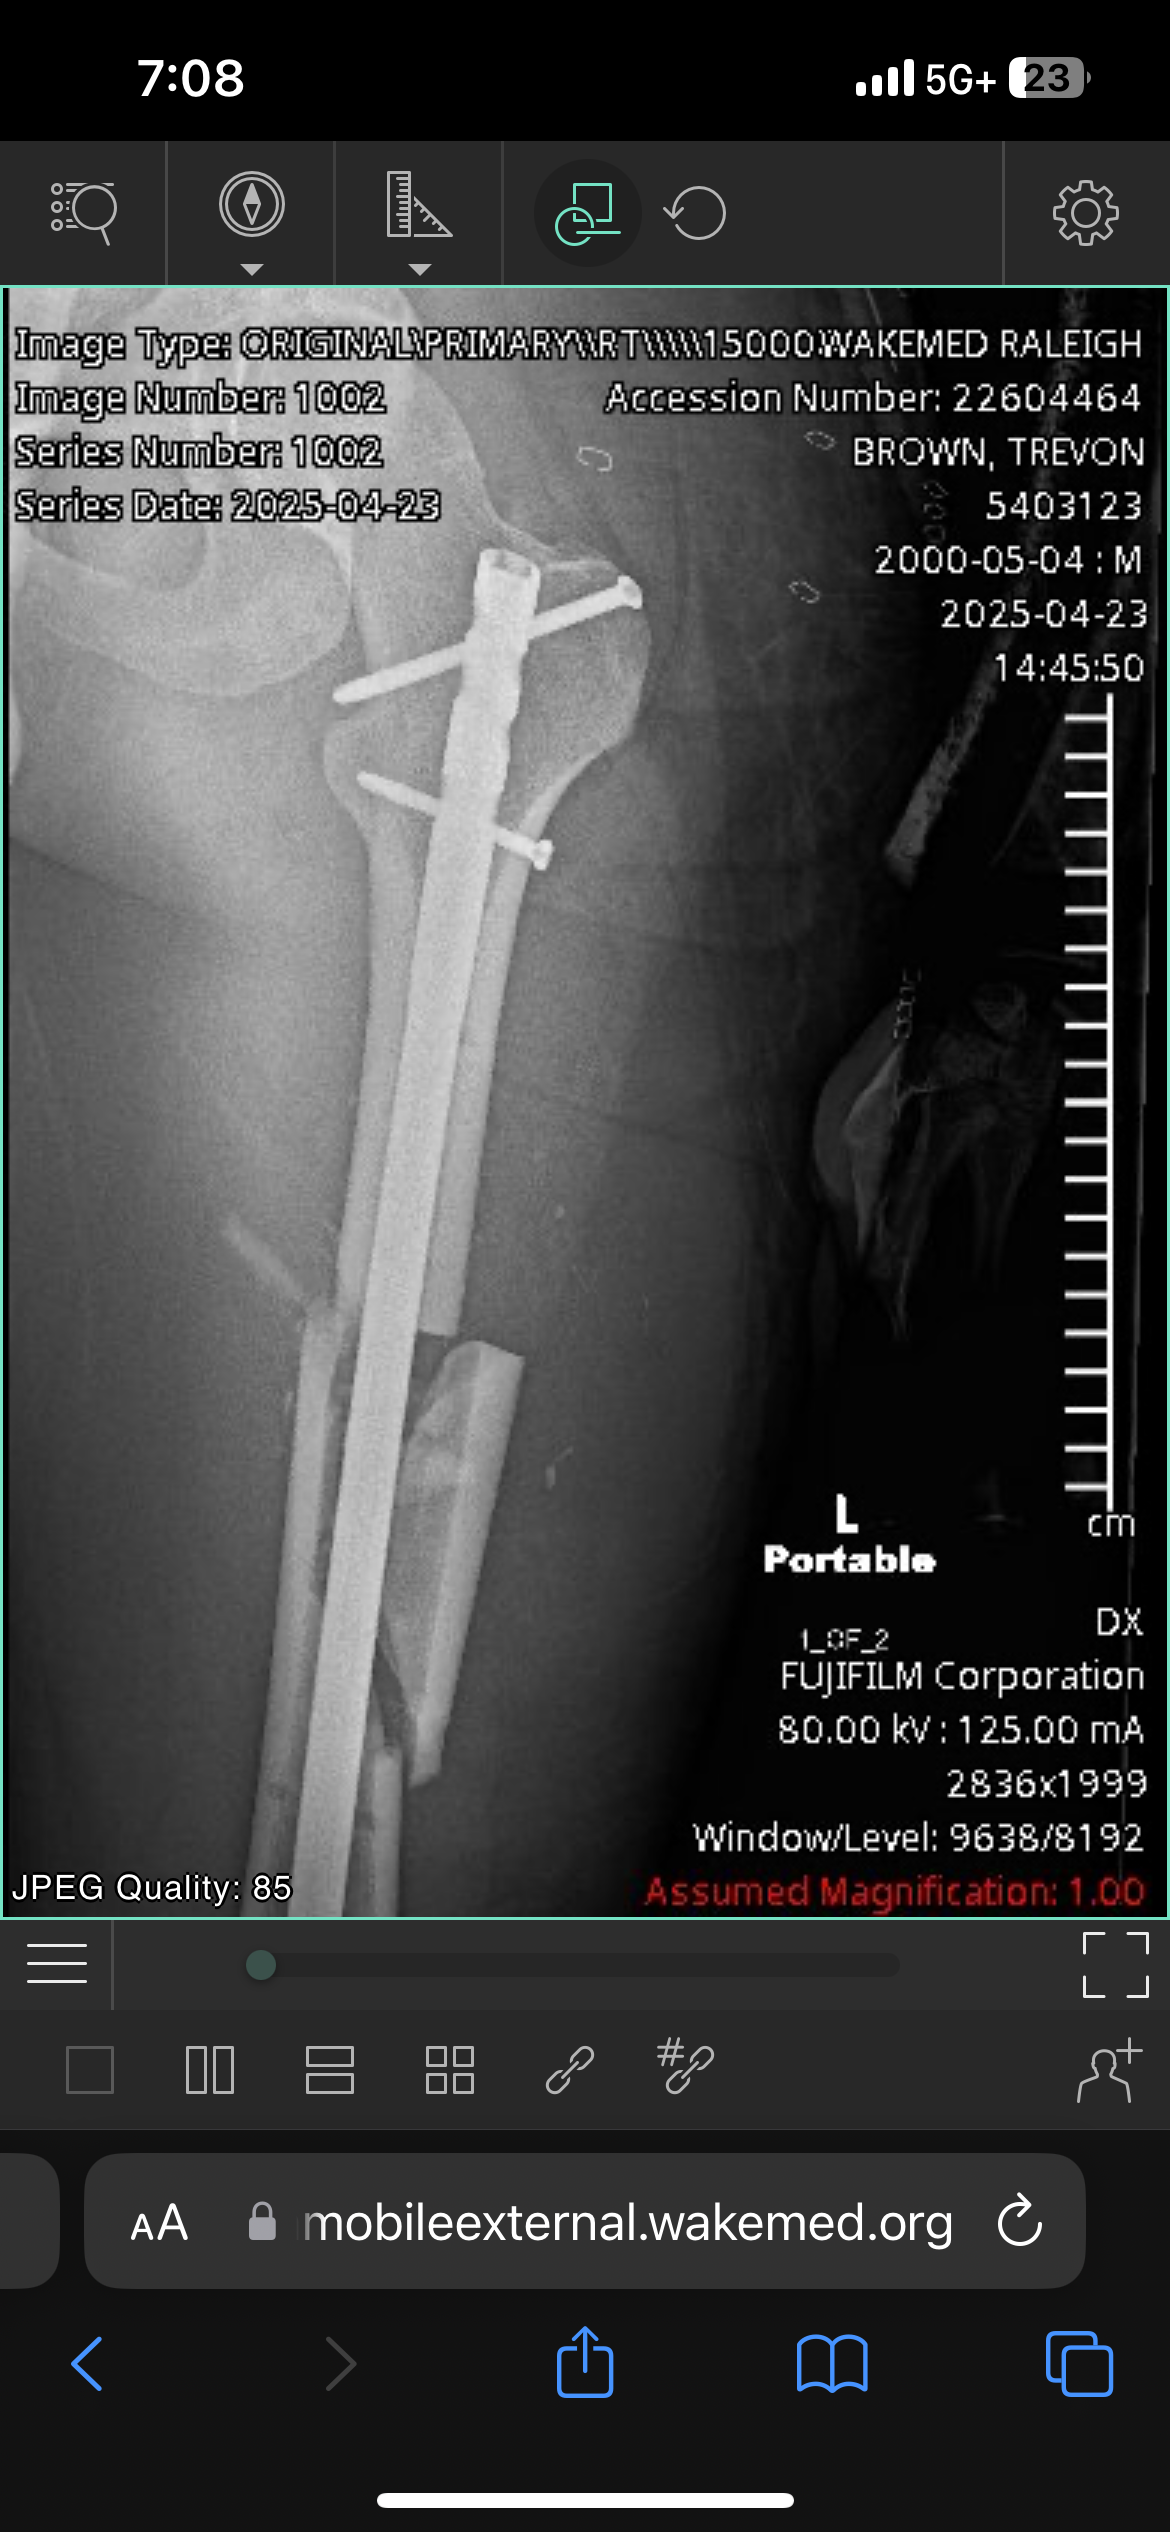

Latrice was diagnosed with a broken Femur along with a few scrapes and gashes.

Lastly, I was diagnosed with a broken femur, shattered arm, broken neck, ruptured diaphragm and various other injuries but by God, we’re still here!!!